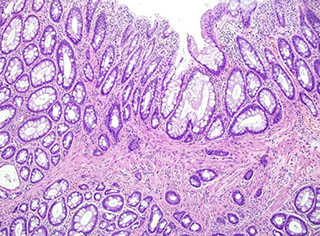

Crohn disease

- aka regional enteritis, granulomatous enterocolitis, terminal ileitis

Chronic, relapsing and remitting c skip lesions affecting multiple portions of the GI  tract from mouth to anus (though rectum usually spared), M=F, peaks in 3rd decade; whites > other races

- Jews> non-Jews

- despite skip lesions, will see deep, transmural inflammation c cobblestone mucosa, creeping fat, fissures, fistulas (goes all the way through the wall!) causing the wall to be thick (vs thin in UC)

- can have cramping pain in RLQ (mimics acute appendicitis), have abdominal mass and non-bloody diarrhea, weight loss and Fe-def anemia (mimics celiac dz)

- grossly see apthous erosions, longitudinal (tram track) ukcers, and adjacent areas unaffected; also cobblestoning

- rectum usually spared and ileum affected (vs UC)

- can get cutaneous granuloma, called metastatic Crohn disease

- fibrosing strictures common, and require excision

- extraintestinal manifestations: uveitis, migratory polyarthritis, sacroileitis, ankylosing spondylitis, erythema nodosum, finger clubbing, pericholangitis, PSC

- Th1 cells polarized, Th17 cells as well as IL-23 receptor polymorphisms

Micro: noncaseating granulomas (seen in ~1/2 of surgical cases; though not specific [also seen in some immune conditions {CGD}]) and lymph aggs, crypt abscesses, architectural distortion, Paneth cell metaplasia in left colon where you dont usually see Paneth cells,

- lymph aggs seen as "sting of pearls"

- some areas may be completely normal

- regions of pyloric metaplasia indicate inflam and repair

- basal plasmacytosis seen in UC and Crohn

- May appear similar to reaction to mycobacteria, possibly bc genes involved in mycobacteria infx same as those in Crohn (NOD2, IRGM)

Complicated by fissures and fistulas

- fissures occur bwt bowel loops and other hollow organs, or can just perforate into abdominal cavity

Labs: Anti Saccharomyces cervisiae antibody (ASCA) (+) and ANCA negative (vs UC)

- has Th1 inflammation

Genetics: (Caspase Recruitment Domain) CARD and NOD2 protein which is signal transducer for inflammatory cells which are activated by bacterial products

Dx: need to r/o malignancy c bx

DDx: infx colitis, rx-colitis, UC

Tx: roids (for acute flares), infliximab, metronidazole may prevent

- screening: after 8-10 years of colonic involvement scope em every 1-2 years

Px: Inc risk of colon ca (which is mucinous and usually poorly-diff)